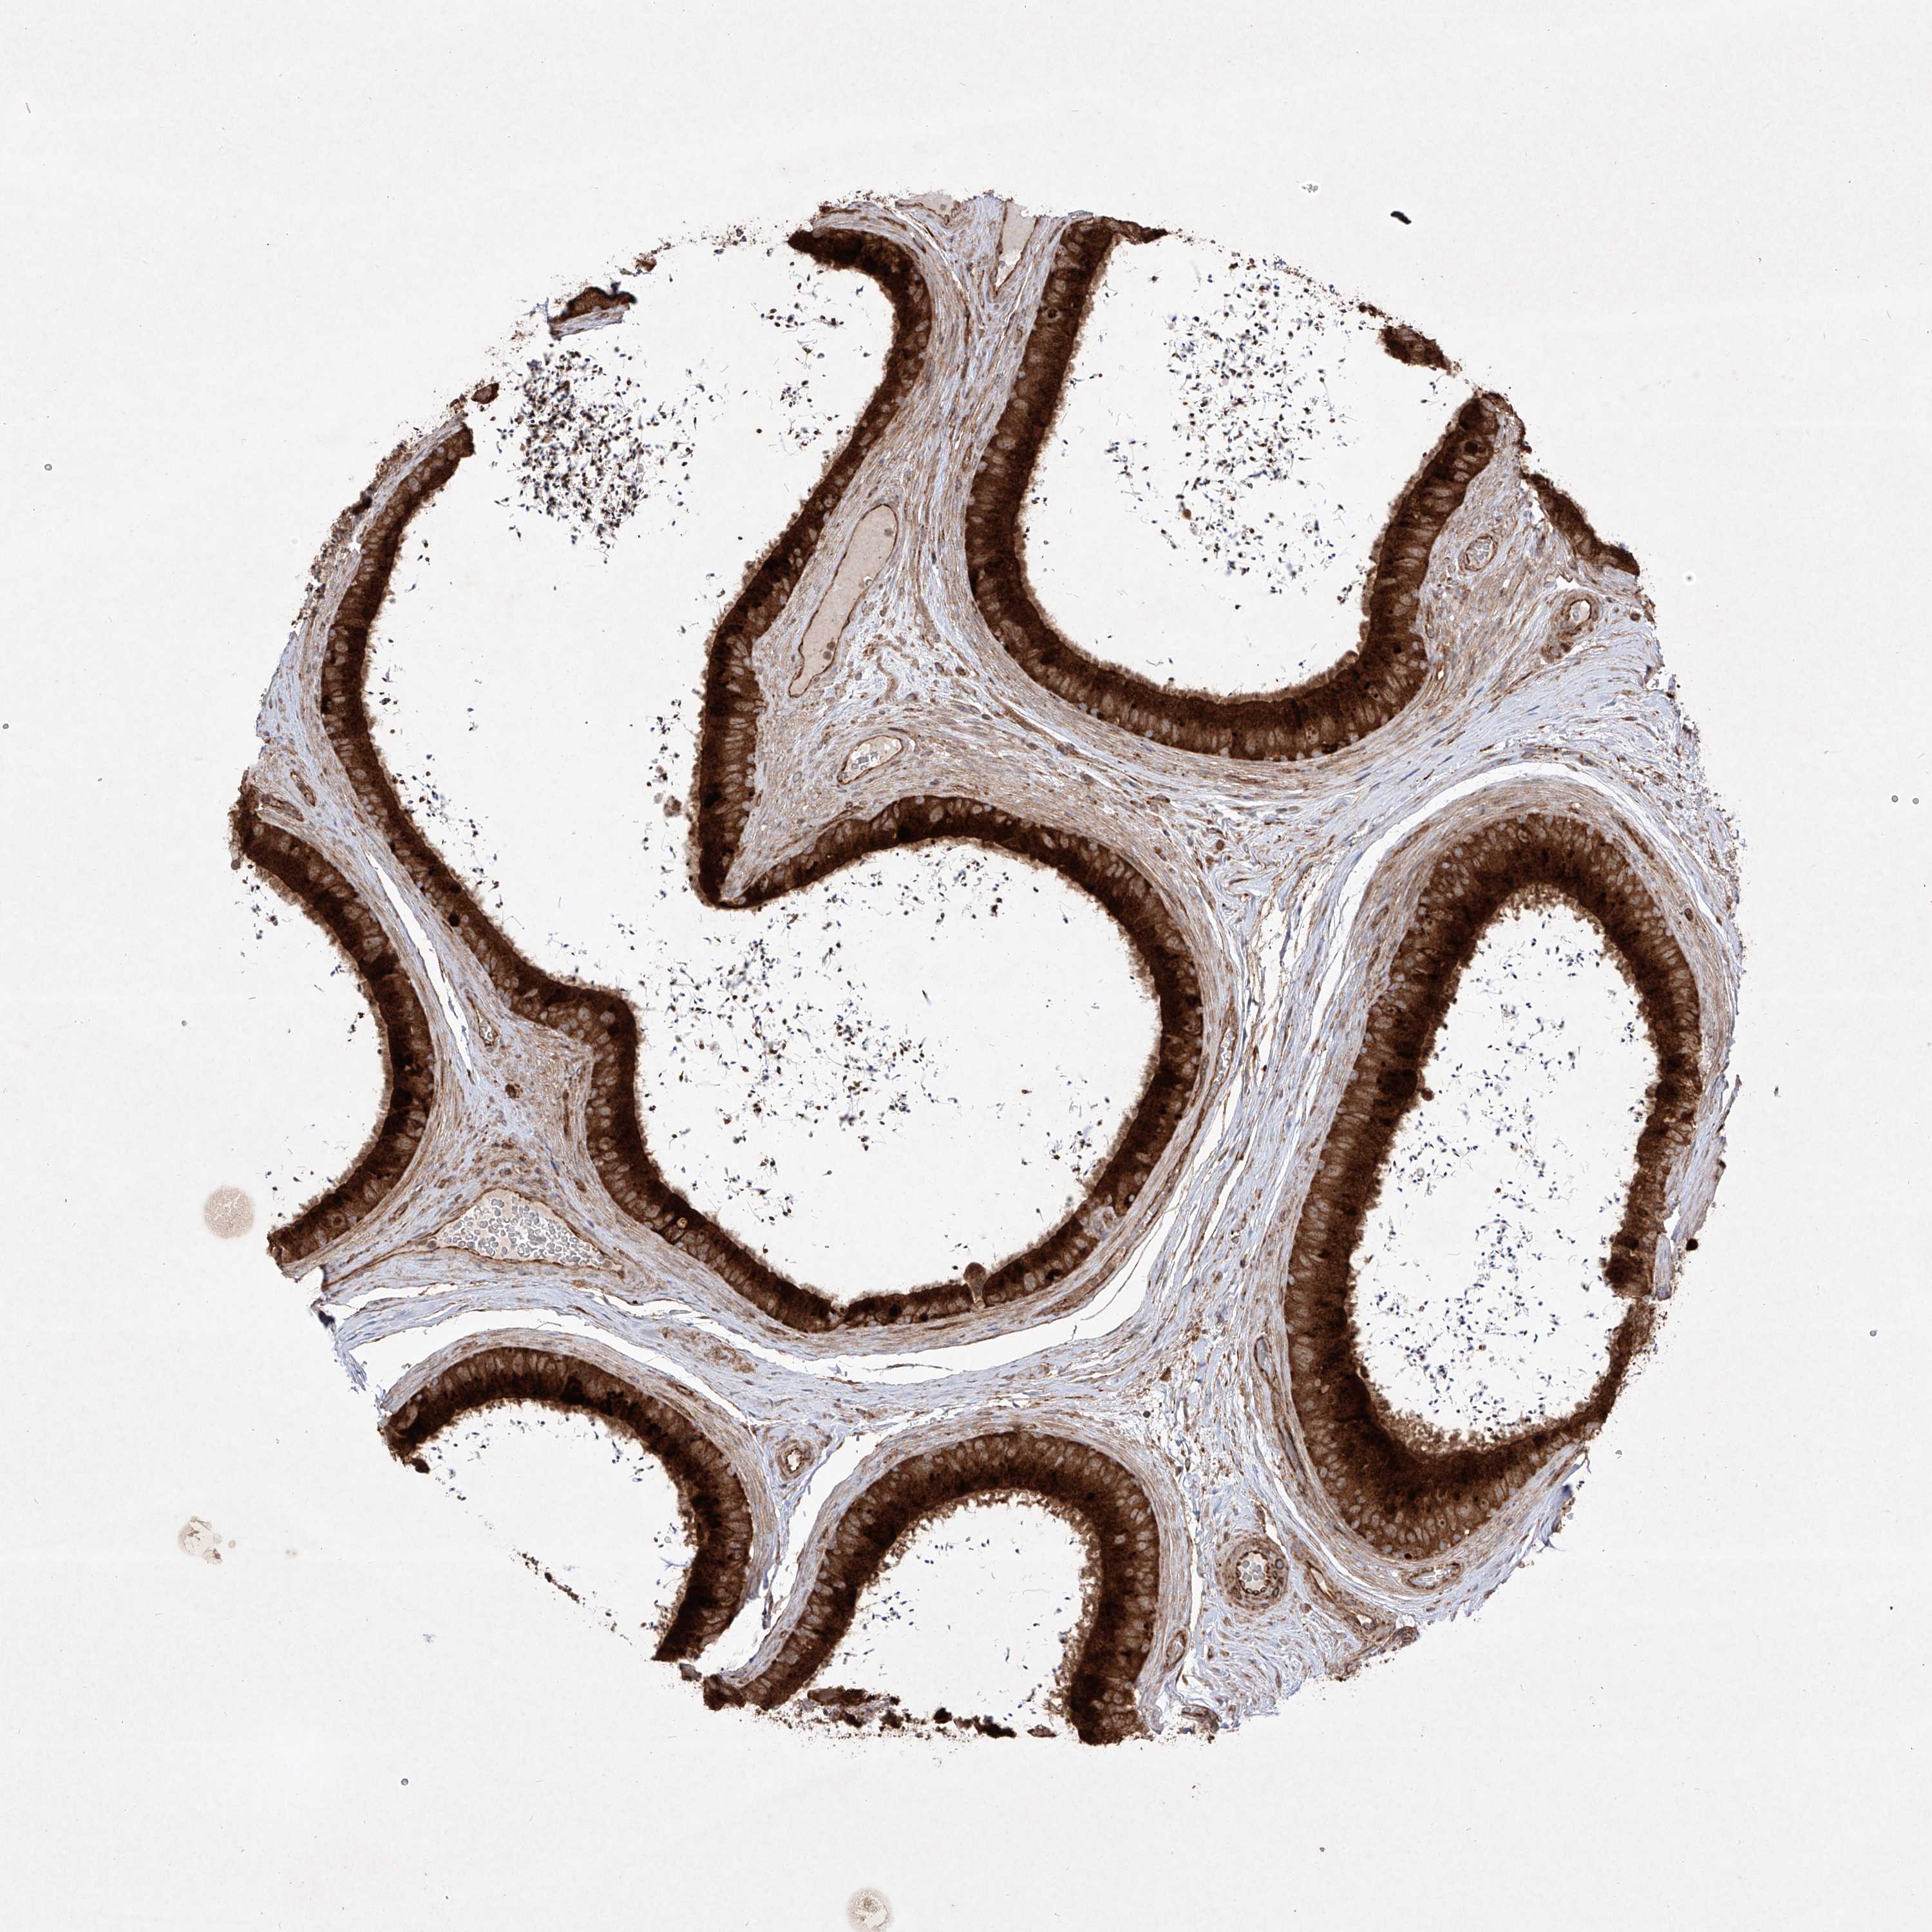

TISSUE PRIMARY DATA EPIDIDYMIS Show tissue menu

EPIDIDYMIS - Antibody stainingi

Antibody staining in the annotated cell types in the current human tissue is reported as not detected, low, medium, or high, based on conventional immunohistochemistry profiling in selected tissues. This score is based on the combination of the staining intensity and fraction of stained cells.

Each image is clickable and will lead to virtual microscopy that enables deeper exploration of all samples and also displays staining intensity scores, fraction scores and subcellular localization as well as patient and tissue information for each sample.

Antibody HPA030817Antibody HPA030818

Glandular cells HighMedium